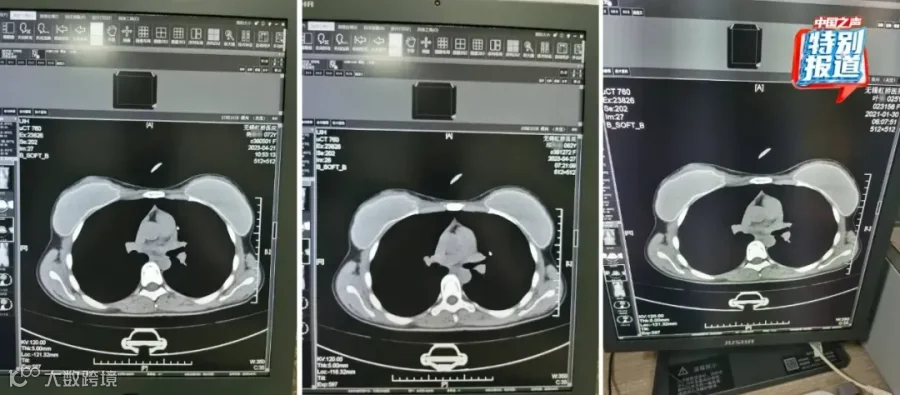

9月23日,国家医保局官方微信公众号发文称,针对近期网上举报的无锡虹桥医院涉嫌欺诈骗保问题,国家医保局派出飞行检查组,于今日上午进驻该院开展专项飞行检查。